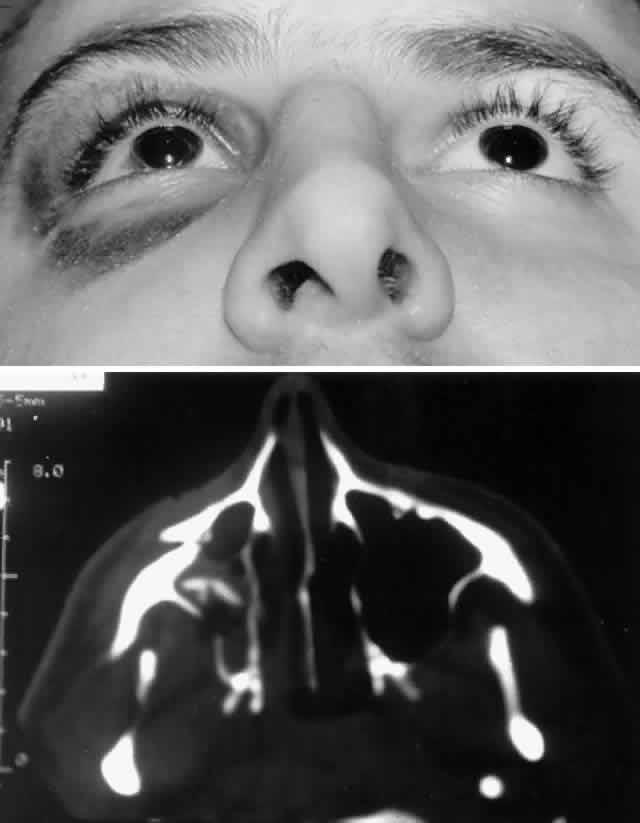

with stainless steel, with titanium having the least artifact.  Fig. 8. A. Patient with right zygomatico-orbital fracture. Note flattening of right

malar eminence and slight right lateral canthal dystopia. B. Axial CT scan shows displaced right zygomatico-orbital fracture. Fig. 8. A. Patient with right zygomatico-orbital fracture. Note flattening of right

malar eminence and slight right lateral canthal dystopia. B. Axial CT scan shows displaced right zygomatico-orbital fracture.

|